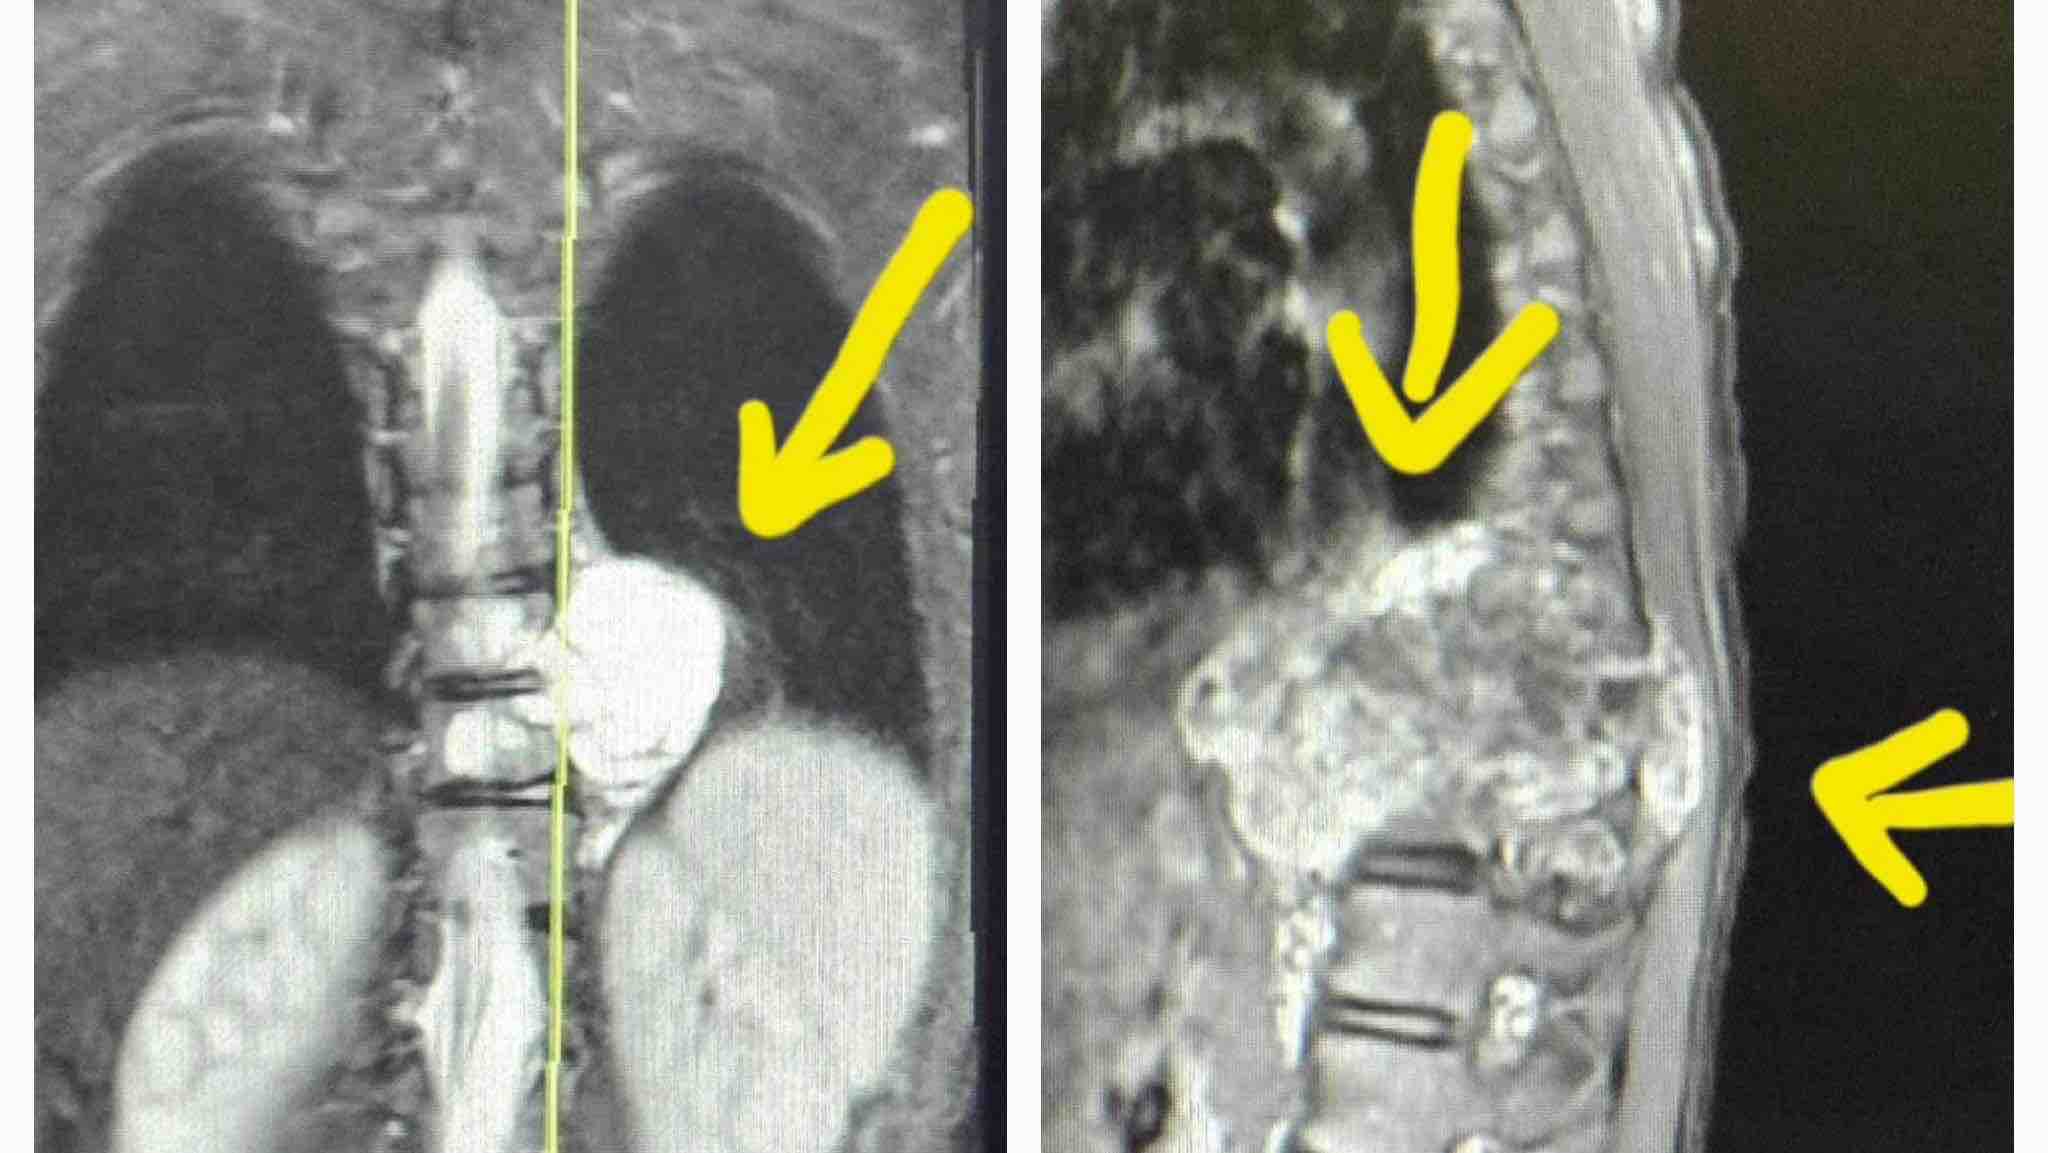

On Sunday, July 28, I took Alexandria to Akron Children's ER. An MRI revealed a tumor on her spine that runs behind her lung and into her spinal cavity, wrapping around her spinal cord and causing it to bend. The tumor is also right up against the aorta- a major artery. It spans over a large area of her chest cavity and vital organs.

Emergency surgery was performed to remove as much of the tumor as possible from the spinal cavity to relieve pressure on the spinal cord and hopefully restore some function to her legs. The tumor has also damaged the bones in her spine, requiring reinforcement or reconstruction of sections of her spine to prevent collapse when the tumor is removed.